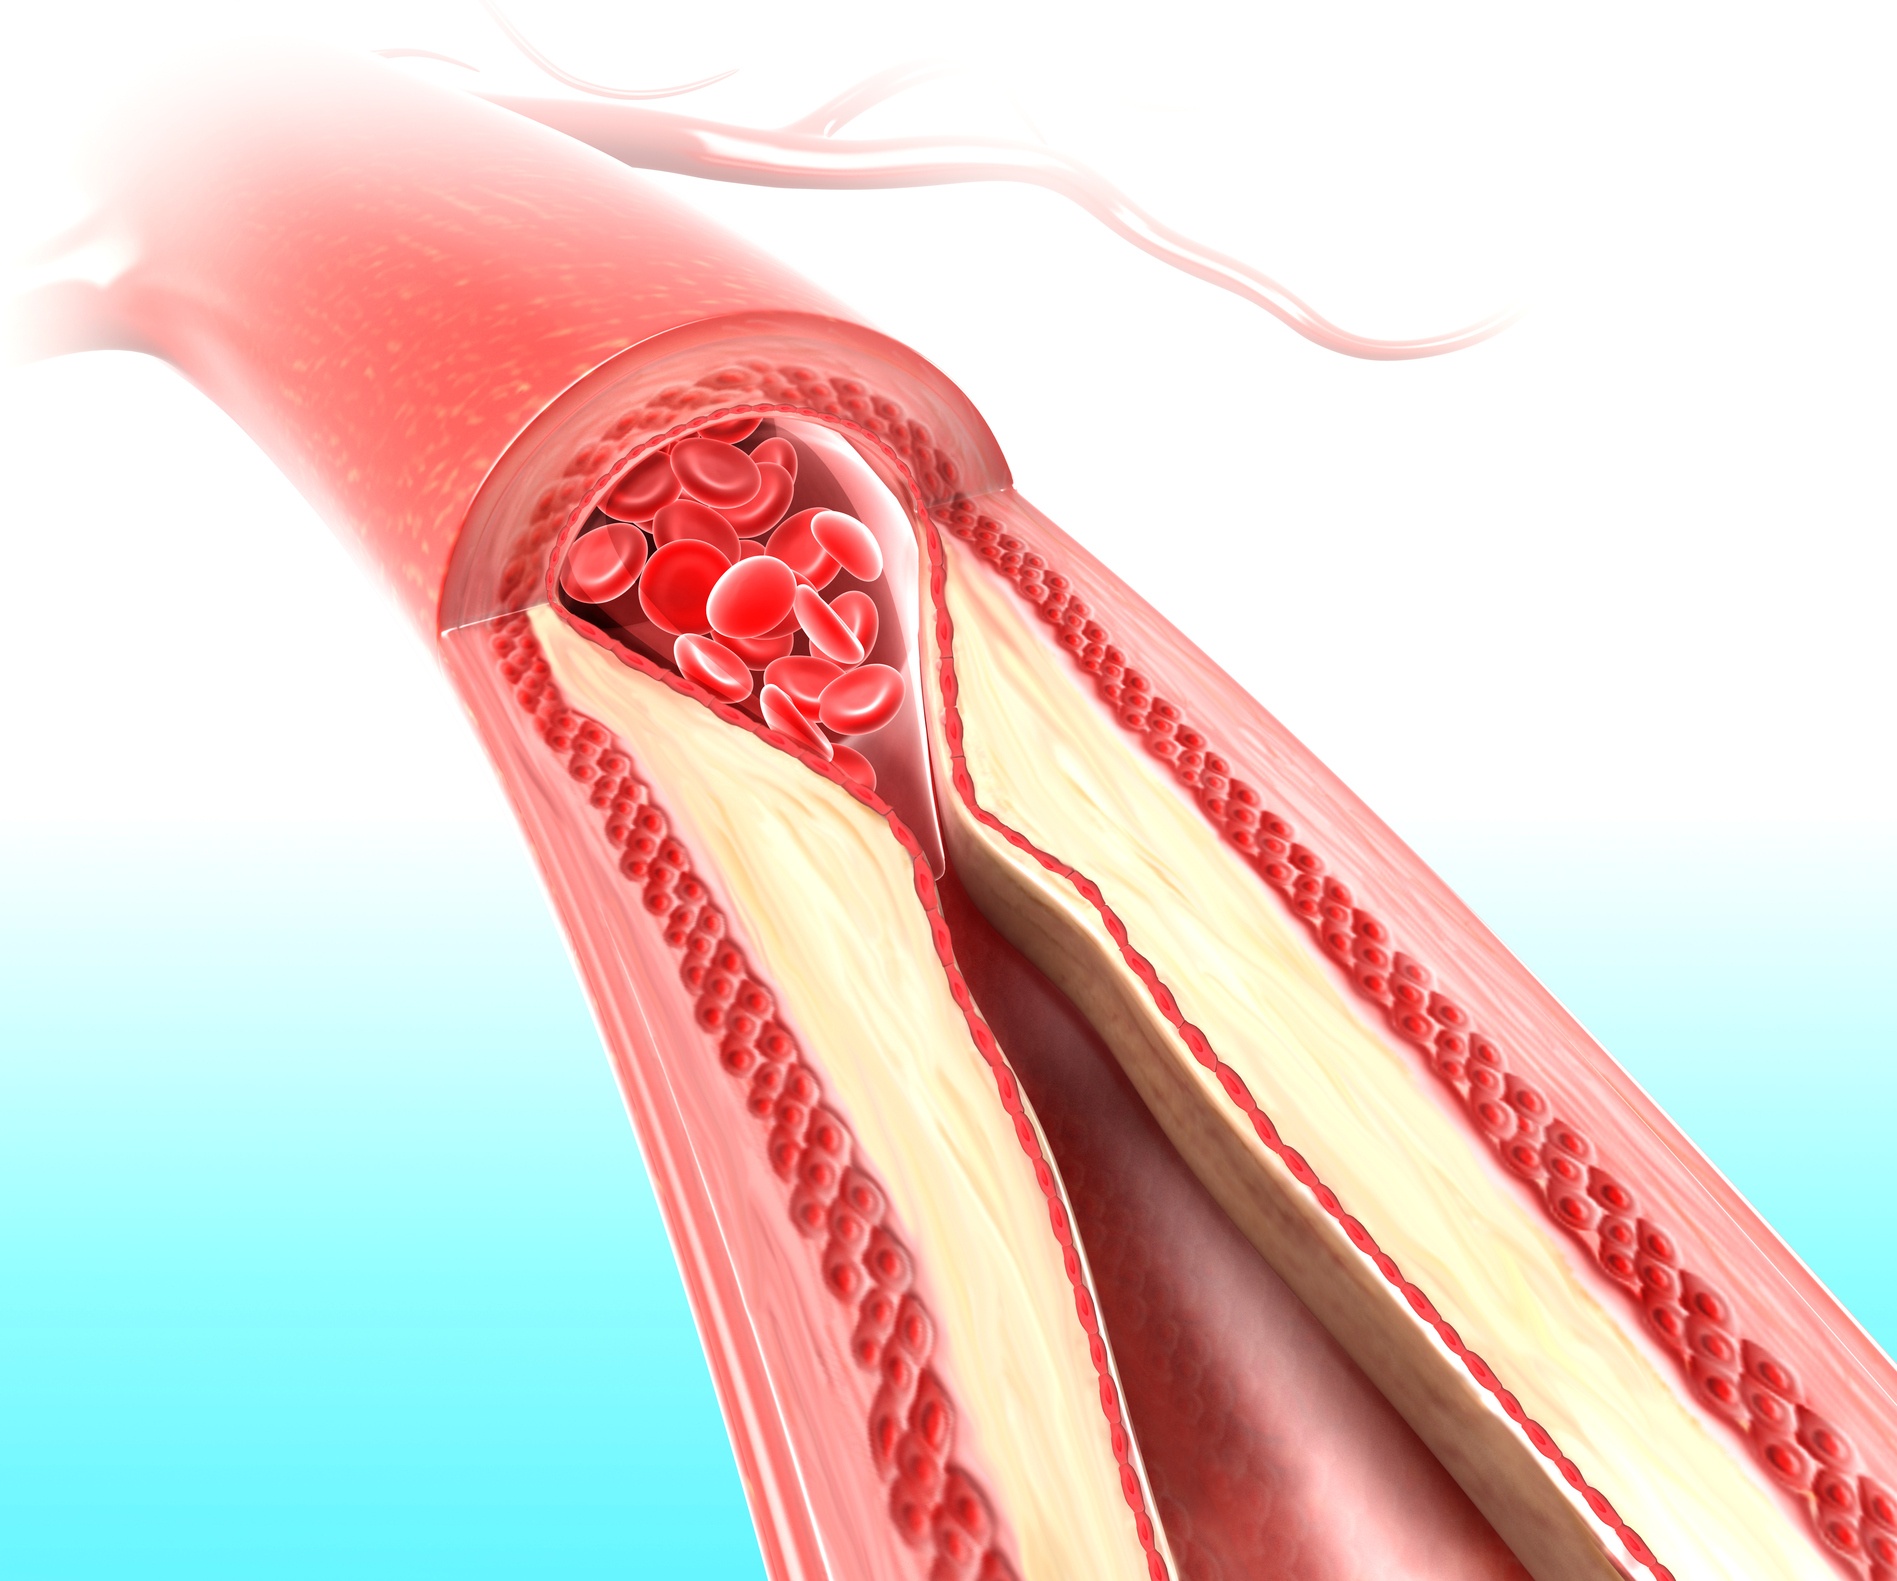

Хроническая окклюзия артерий: причины, симптомы и лечение